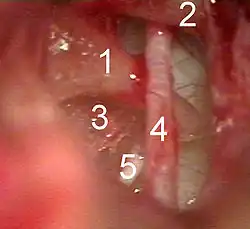

![]() Vista del oído medio tras una incisión quirúrgica del tímpano, con la cuerda del tímpano en primer plano (4). | ||

La cuerda del tímpano, también conocida como raíz parasimpática del ganglio submandibular (chorda tympani, radix parasympathica submandibularis) es un haz de fibras parasimpáticas (para el ganglio submandibular) y simpáticas, procedentes de las papilas gustativas de los dos tercios anteriores de la lengua. Se extiende de forma recurrente hacia la cavidad timpánica, pasa entre el martillo y el yunque y emerge de la cavidad timpánica por la abertura del conductillo de la cuerda del tímpano, excavada en el espesor de la fisura petrotimpánica, para terminar en el nervio lingual.[1] Es una rama del nervio facial (par craneal VII) que conecta las papilas gustativas de esa parte de la lengua y lleva sus mensajes al cerebro. Recoge la sensibilidad gustativa de los 2/3 anteriores de la lengua.